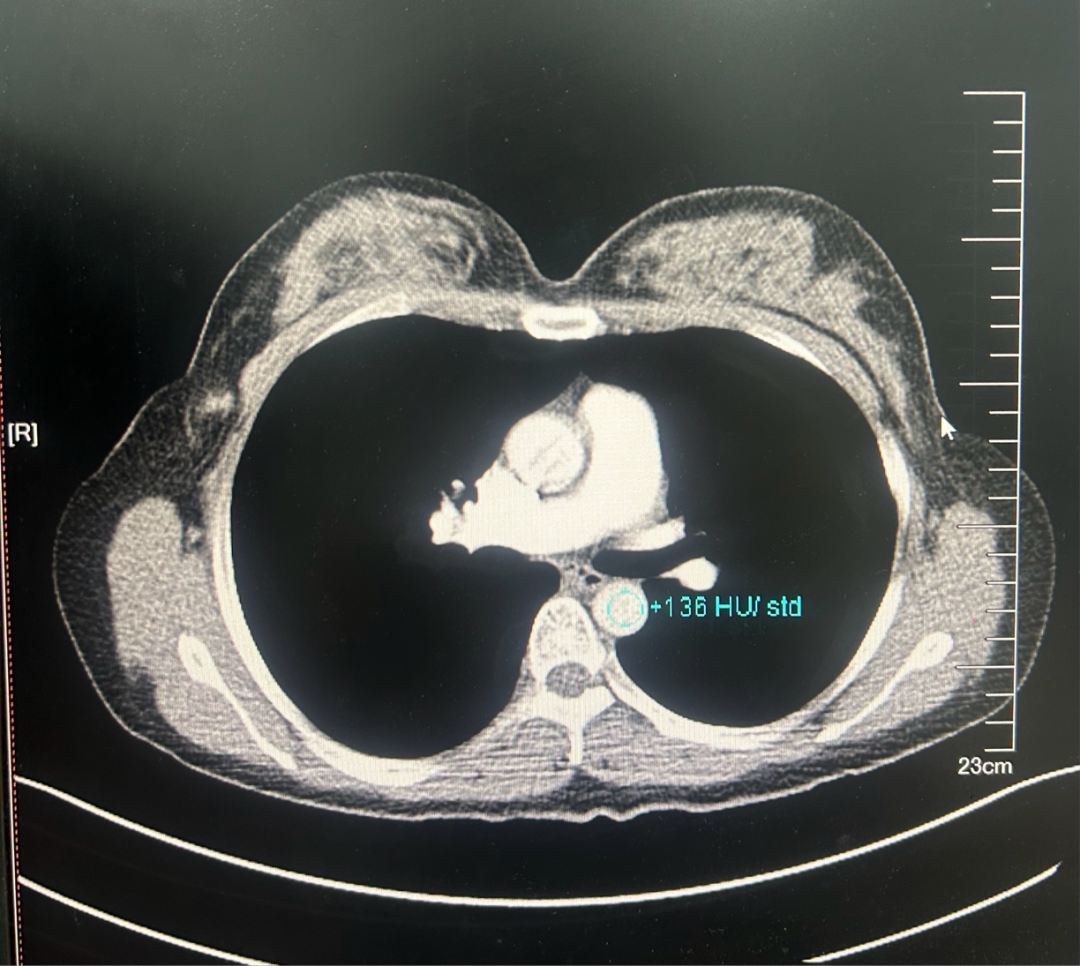

·CT

图4.2023年6月27日CT结果

1、双肺肺气肿并散在肺大疱。

2、双肺多发微小结节,多为磨玻璃结节,密切随诊。

3、左乳外份肿块,建议乳腺相关检查。